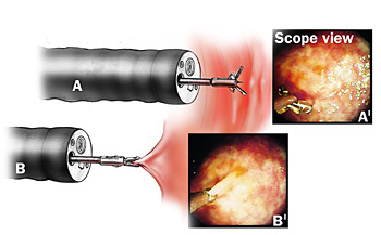

Se necessário, pequenas amostras de tecido (biópsias) podem ser colhidas durante o exame para análise microscópica detalhada. Não se preocupe, não dói.

Mucosectomia é o procedimento realizado quando há necessidade de retirada de lesões maiores do trato gastrointestinal.

O exame de Mucosectomia é realizado através de injeção de liquido embaixo da lesão, através de uma agulha específica. Com isso a lesão se destaca das camadas mais profundas do intestino, diminuindo o risco de perfuração.

A retirada da lesão é feita com uma alça de polipectomia e o material é encaminhado para estudo anatomopatológico (no microscópio) da mesma forma que ocorre nas biópsias.

Geralmente apenas uma região do pólipo é que se apresenta de forma cancerosa. Se for realizada uma simples biópsia do pólipo, a região cancerosa pode não ser atingida e o diagnóstico de câncer não ser realizado. Para se ter certeza do diagnóstico, o pólipo inteiro deve ser removido através do procedimento chamado de polipectomia.

O que é a polipectomia?

A polipectomia é a remoção completa de um pólipo permitindo assim o diagnóstico exato e muitas vezes a cura do próprio problema. Existem várias técnicas para a realização do procedimento que dependem do tamanho e do tipo de pólipo a ser ressecado.

Polipectomia com pinça

Pequenos pólipos podem ser removidos com segurança usando-se apenas uma pinça.

Polipectomia com alça diatérmica

Pólipos maiores necessitam ser removidos com alça e corrente de cauterização. Este procedimento permite cortar a base do pólipo e ao mesmo tempo coagular o local para evitar sangramentos.

Porém alguns pólipos possuem a base (pedículo) largo onde passam vasos calibrosos e por isto tem risco aumentado de sangramento na retirada mesmo usando a corrente de coagulação.

Nestes casos algumas medidas podem ser realizadas para diminuir o risco de sangramento:

Injeção de adrenalina na base do pólipo

Colocação de um laço na base do pólipo para estrangular o pedículo

Alguns pólipos são tão grandes que não podem ser removidos inteiros. Nestes casos o pólipo é retirado em pedaços para poder garantir a sua remoção completa.

Alguns pólipos não possuem a base alongada (pedículo), estes são chamados de pólipos sésseis. A remoção destes pólipos possui risco maior de perfuração do órgão pois como são planos ficam muito próximos da parede externa do órgão.

Mucosectomia

Para diminuir este risco, injeta-se com um uma agulha uma solução abaixo do pólipo para que ele levante e fique mais longe da parede do órgão. Após isto passa-se a alça diatérmica e realiza-se o

procedimento de polipectomia.